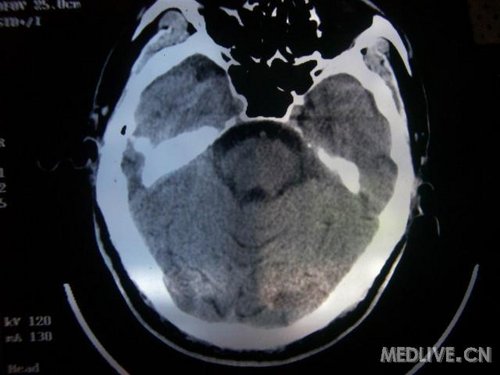

病人男性 73岁 市民 以“幻听、幻视两天,言语含糊、精神错乱一天”入院。

两天前无诱因出现幻听、幻视,描素眼前有彩色的圆圈,听见有人说话(但说什么不详),一天前出现胡言乱语,言语含糊,精神错乱,问话不答,行走略有不稳,来我院就诊,门诊头CT检查:(下面有片)入院后查体不合作,表情淡漠,问话不答,大致检查了一下,颅神经未见明显异常,颈软,右手活动似忽略差。其他检查不配合。脑电图:广泛轻-中度异常。

既往史:半年前曾患“右侧脑梗塞”但无明显后遗症,生活能自理,无高血压、糖尿病、心脏病史。

此次入院时的片子: